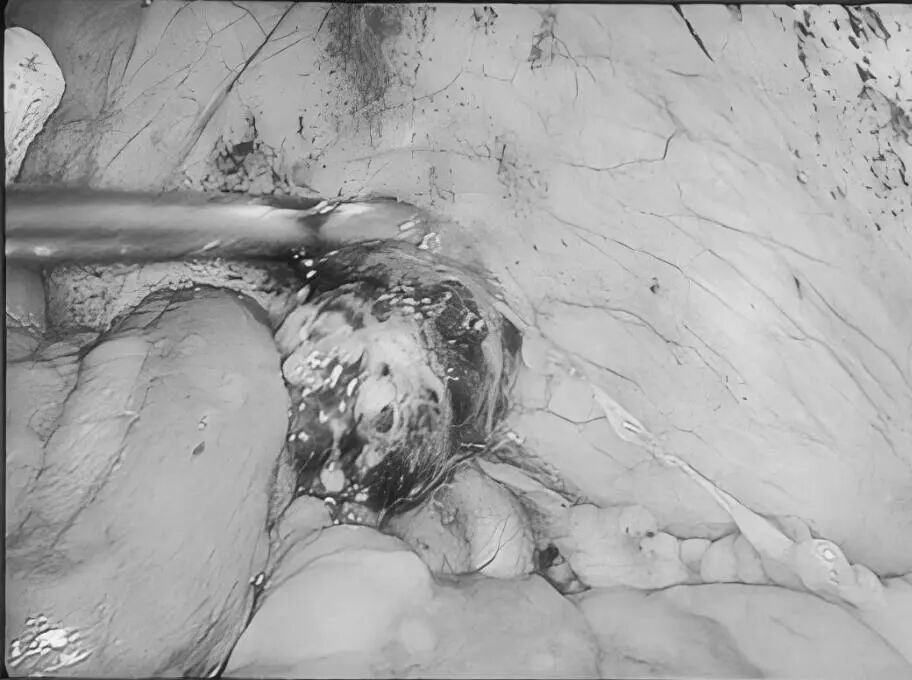

近日,贵州航天医院普外科特邀贵州医科大学附属医院胃肠外科严芝强博士前来我院开展“腹腔结核的综合治疗”学术讲座,严博士结合临床实际案例,带来了腹腔结核综合治疗的前沿知识和宝贵经验,深入浅出地讲解了腹腔结核的发病机制、诊断要点、最新治疗策略及药物精准治疗、把握手术干预时机、营养支持等关键环节,为提升我院腹腔结核诊治水平奠定了坚实基础。 今天,小编就带领大家回顾讲座内容,你想要了解“腹腔结核”知识都在这里! 什么是腹腔结核? 结核病是由结核分枝杆菌引起的传染病,曾是单一传染源死亡的主要原因,能影响身体多个器官,腹腔结核就是其中之一,包括胃肠道、腹膜、肠系膜淋巴结等部位的结核病。 腹腔结核常见症状 消化系统症状:常见为腹痛,可能伴有呕吐、腹胀、恶心、腹泻或便秘等症状。如:频繁呕吐,无法正常进食;长期受腹胀困扰,腹部隆起。 全身症状:发热、盗汗、体重减轻等。如:不明原因地体重下降,身体逐渐消瘦,夜间睡觉时大量出汗。 腹腔结核发病原因 消化道感染:食(饮)用带菌牛奶或被结核菌污染食物,进入消化道后,结核菌在肠道淋巴组织中形成病灶,并可能蔓延至肠系膜淋巴结、腹膜等部位。如,经常喝未经严格消毒的牛奶,增加感染风险。 血行播散:身体其他部位的结核菌,通过血液循环到达腹腔,侵犯腹腔内器官。如肺结核,当患者免疫力下降时,结核菌就可能“乘虚而入”进入血液,进而播散到腹腔。 淋巴结播散:胸腔内淋巴结结核或全身粟粒型结核,结核菌可通过淋巴管道传播至腹腔淋巴结,引发腹腔结核。 腹腔结核治疗方式 1.早期、联合、全程规范化抗结核治疗(治疗原则)。 2.加强支持治疗。 3.抗结核化学药物治疗:一般三联或四联。 4.放腹水,可同时腹腔内注射药物治疗。 5.手术治疗:仅限于完全性肠梗阻、肠瘘或并发肠穿孔者,当本病诊断有困难,与腹内肿瘤或某些急腹症不能鉴别时,可考虑剖腹探查。 腹腔结核饮食注意 腹腔结核患者饮食少量多餐,控制高脂、肥腻食物摄入,多吃清淡、易消化的食物,适量补充高蛋白等营养,多吃富含纤维素的新鲜蔬菜和水果,促进肠腔及腔腹部蠕动,禁食辛辣刺激性食物,忌烟酒。 腹腔结核预防建议 如果感染腹腔结核,一定要到正规医院做正规抗结核治疗,积极配合,树立战胜疾病的信心,就能战胜病魔,恢复健康。 近年来,腹腔结核发病率呈上升趋势,因其诊疗复杂、病情多变,常累及肠道、腹膜等多脏器,致患者腹痛、肠梗阻,严重影响生活质量,甚至危及生命。 对此,贵州航天医院普外科依托结核内科结核病诊疗经验,积极开展腹腔结核外科治疗工作,通过内外科联合,着力打造腹腔结核诊疗体系,为遵义地区腹腔结核患者提供更加优质、全面的诊疗服务。 咨询信息:贵州航天医院便民服务电话(请点击跳转咨询电话页面) 注:部分图片来源于网络,如有侵权,请联系删除。 贵州航天医院普外科专家团队 梁 跃 普外科主任 主任医师 临床擅长:对普外科各类肿瘤手术具有丰富的临床经验。 毕业于遵义医学院,遵义市医学会小儿外科学分会常务委员,遵义市肛肠协会理事,遵义市医学会核医学分会(第二届)委员会委员;荣获第三期“黔医人才计划”优秀学员称号;主持市级课题1项,完成省级课题1项,在国内各类刊物上发表论文10余篇。 钱科洪 普外科 副主任医师 临床擅长:从事普外科临床工作30余年,对各类普外科疾病的诊治、乳腺、甲状腺、胃十二指肠、结直肠等疾病及疑难杂症具有丰富的临床诊疗经验。 毕业于遵义医学院临床医疗系,2009年前往中山大学附属第一医院微创外科进修学习,在国内各专业期刊发表论文数篇。 贵州航天医院普外科简介 基本情况 贵州航天医院普外科成立于1968年,前身属于航天部O61基地3417医院外一科,1998年3417医院、3427医院合并后更名为普外科,下设胃肠外科、肛肠外科2个亚专业科室,拥有在全市较为先进的专科设备和技术,是中国疝病专科联盟单位,贵州医科大学附属医院胃肠外科专科联盟单位。开放床位40张,配备医护人员21人。 专科特色 普外科致力于胃肠及肛肠疾病的外科临床诊治及科研,以腹腔镜微创外科技术为本,形成以快速康复治疗胃肿瘤、结直肠肿瘤、小肠肿瘤、直肠脱垂、肥胖病、急腹症、各类疝、痔、瘘等专科特色,同时注重胃肠疾病尤其是结直肠恶性肿瘤的基础研究和临床转化研究,总体诊断和治疗水平在区域同级医院居于领先水平。 开展手术:腹腔镜下胃癌根治术,腹腔镜下袖状胃切除术,腹腔镜下胃肠道间质瘤切除术,腹腔镜下结、直肠癌根治术,胃癌、结直肠癌的精准治疗,腹腔镜下小儿疝气、成人疝修补术,腹腔镜下阑尾手术,内痔的硬化注射治疗及痔疮的微创治疗:ATH、PPH、TST,直肠脱垂的各种手术治疗,难治性伤口VSD技术,鼻胃肠管、肠梗阻导管置入术,肛肠术后间歇性导尿技术,并引进了中医适宜技术,也为各种化疗患者提供输液港安装,提高患者就医体验。 腹腔镜下腹股沟疝无张力修补术 腹腔镜下腹股沟疝 无张力修补术 腹股沟疝里金斯坦(Lichtenstein)手术 PPH微创术治疗环状混合痔 黏连性或炎性肠梗阻-肠梗阻导管 腹腔镜袖状胃切除 腹腔镜阑尾切除术 腹腔镜阑尾肿瘤切除术 腹腔镜下结肠癌根治术 诊疗范围 胃肿瘤、结直肠肿瘤、小肠肿瘤、肥胖症、各类急腹症、腹部外伤、腹壁疝、便秘、直肠脱垂、痔疮、肛瘘、肛裂等胃肠、肛肠外科疾病。 END